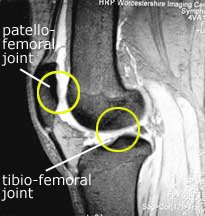

There is a second classification system which is really the basis of all of arthrofibrosis, and that is the anatomic classification. This system identifies where the scar tissue has developed, which is what needs to be surgically addressed.

First, I will provide you with an overview of general anatomy so that we have a common starting point. Then I will discuss the anatomy as it directly relates to arthrofibrosis.